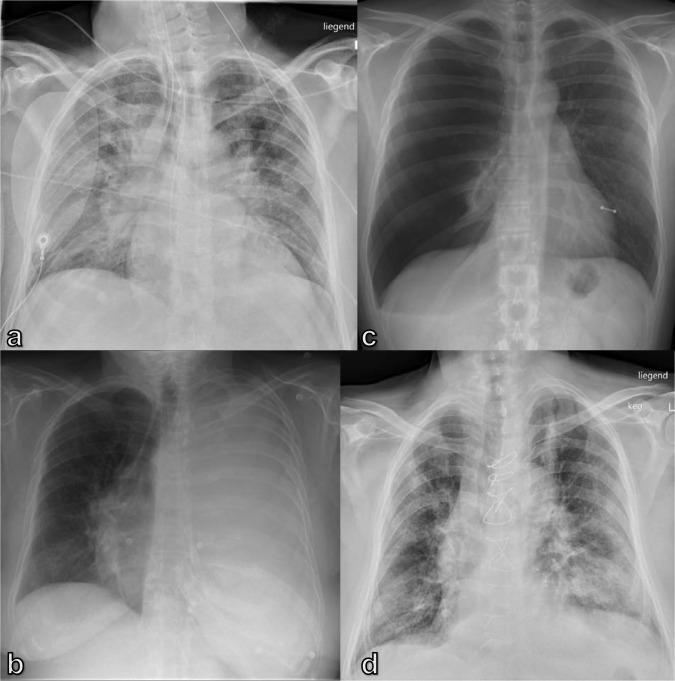

Imaging in patients with acute dyspnea when cardiac or pulmonary origin is suspected.

A wide spectrum of conditions, from life-threatening to non-urgent, can manifest with acute dyspnea, thus presenting major challenges for the treating physician when establishing the diagnosis and severity of the underlying disease. Imaging plays a decisive role in the assessment of acute dyspnea of cardiac and/or pulmonary origin. This article presents an overview of the current imaging modalities used to narrow the differential diagnosis in the assessment of acute dyspnea of cardiac or pulmonary origin. The current indications, findings, accuracy, and limits of each imaging modality are reported. Chest radiography is usually the primary imaging modality applied. There is a low radiation dose associated with this method, and it can assess the presence of fluid in the lung or pleura, consolidations, hyperinflation, pneumothorax, as well as heart enlargement. However, its low sensitivity limits the ability of the chest radiograph to accurately identify the causes of acute dyspnea. CT provides more detailed imaging of the cardiorespiratory system, and therefore, better sensitivity and specificity results, but it is accompanied by higher radiation exposure. Ultrasonography has the advantage of using no radiation, and is fast and feasible as a bedside test and appropriate for the assessment of unstable patients. However, patient-specific factors, such as body habitus, may limit its image quality and interpretability. Advances in knowledge This review provides guidance to the appropriate choice of imaging modalities in the diagnosis of patients with dyspnea of cardiac or pulmonary origin.